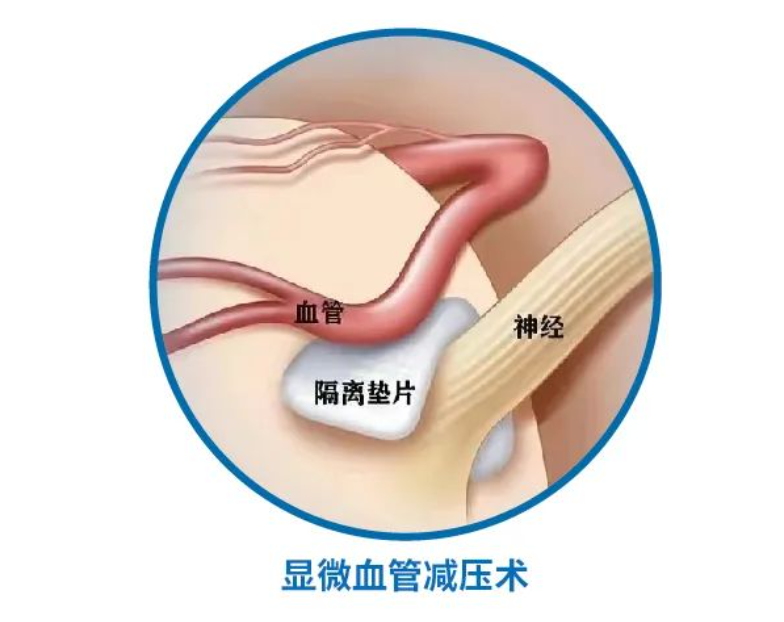

微血管减压术在面肌痉挛患者中的应用

微血管减压术在面肌痉挛患者中的应用

总结背景:面肌痉挛是一种运动性神经紊乱,表现为面部神经所支配的肌肉发生短暂的或持续的无意识收缩。发病率约为11/十万人。